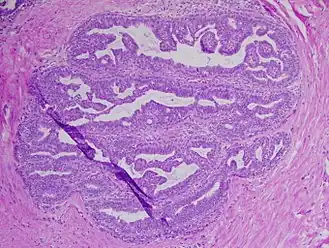

Image histologique de papillome urothélial.

Papillome urothélial inversé de la vessie. HE, x400.